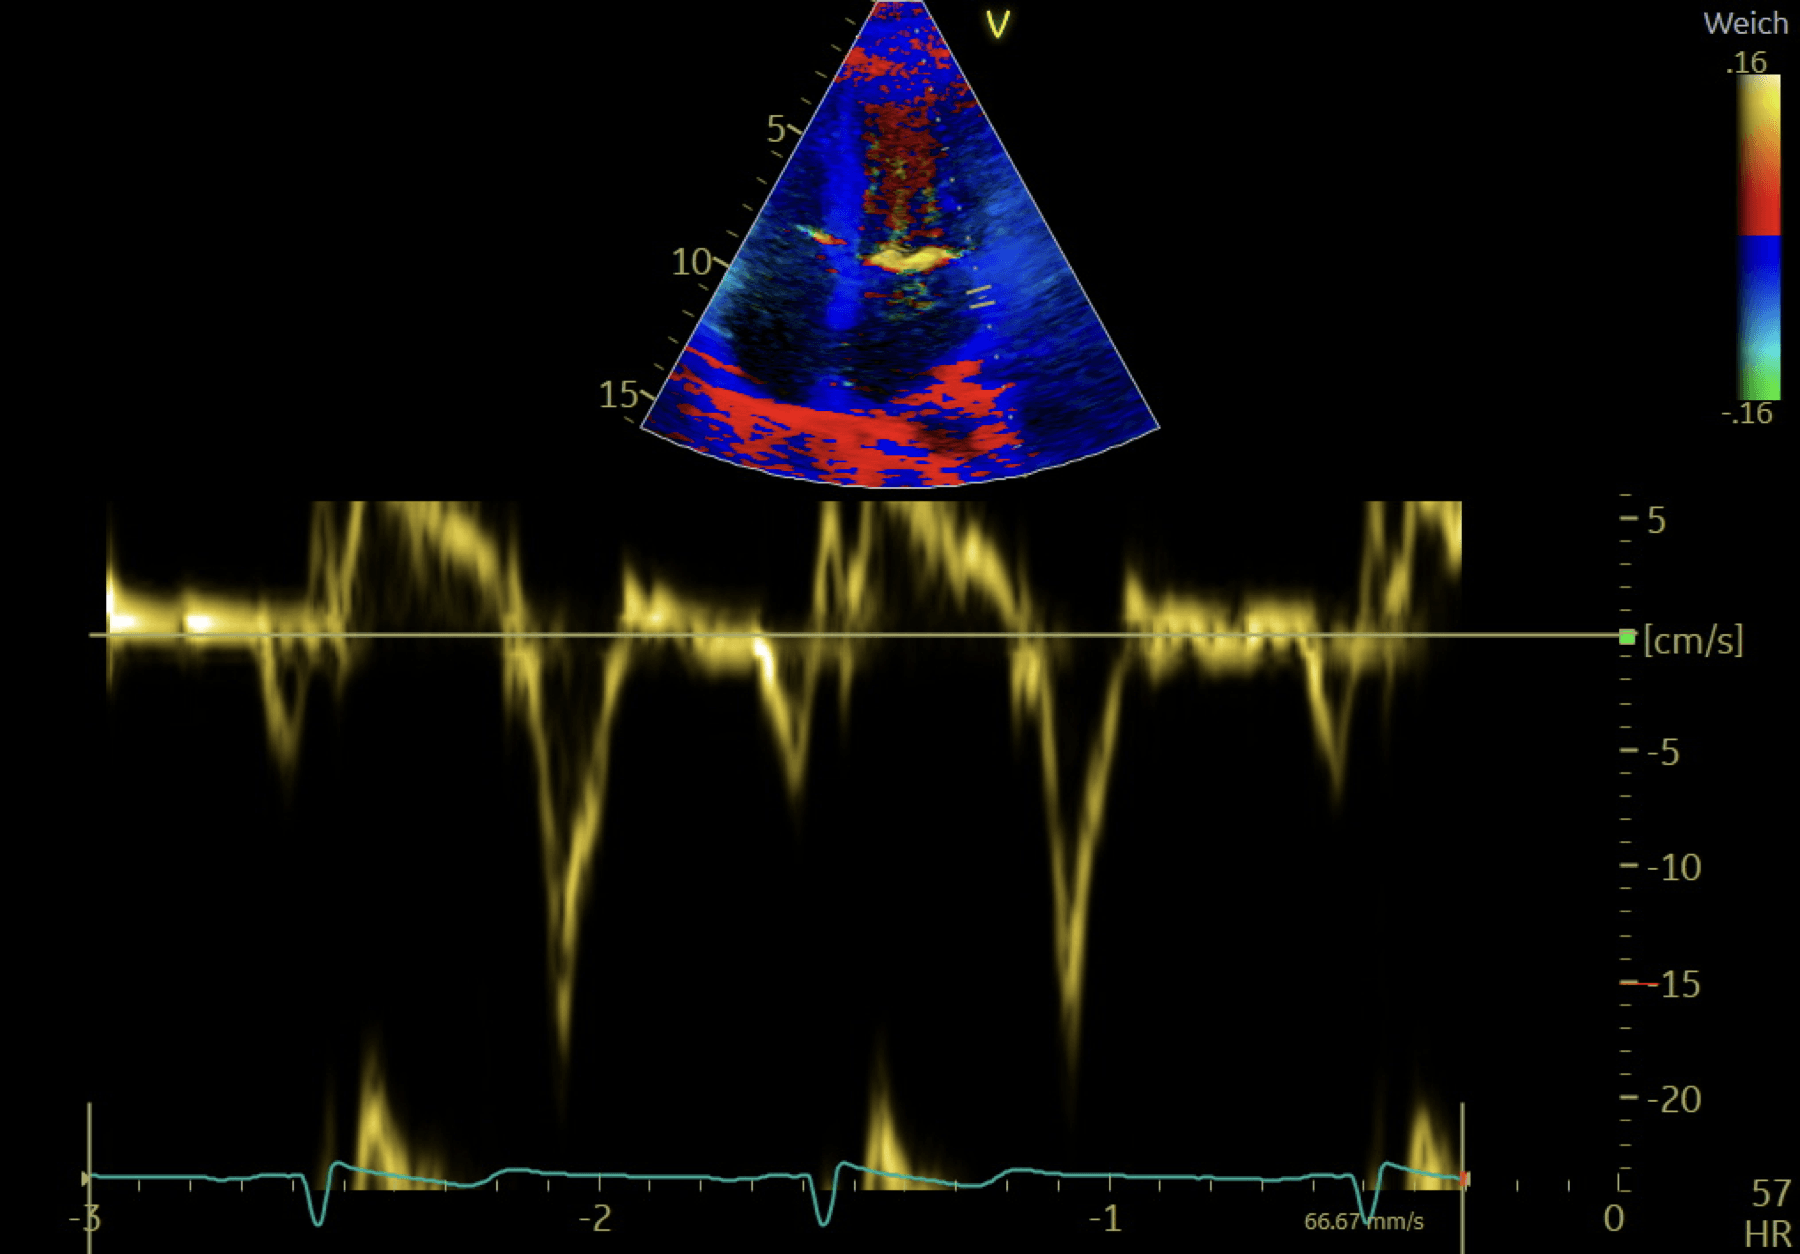

Early filling (E-Wave)

Due to untwisting & relaxation, the LV pressure drops, LAP is higher than the LV pressure, the suction opens the MV ➜ end of the IVRT & beginning of the E-wave. A short (30-40ms) period lowers the LV pressure even though the LV volume expands ➜ a gradient from LA to LV ➜ flow acceleration

80-90% of the blood volume is sucked into the LV during this time (duration around 140ms)